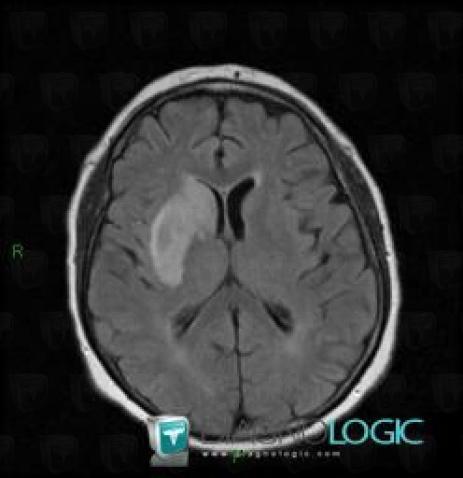

Cerebral infarction, Basal ganglia and capsule, MRI

Here is the specific information in the key image above:

- Diagnosis Cerebral infarction, Location(s) Basal ganglia and capsule, with gamuts Basal ganglia T2W or FLAIR hyperintense lesion